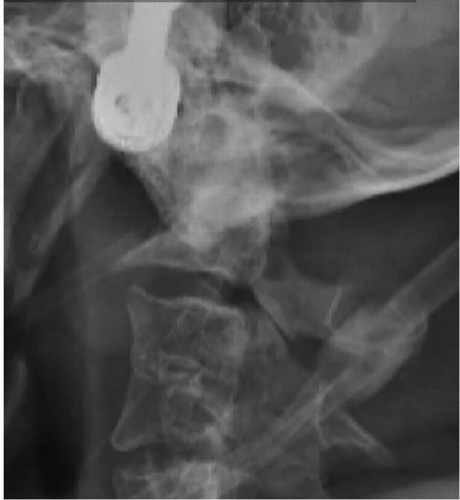

A 51-year-old male presented to us with numerous craniocervical developmental abnormalities and severe cervical myelopathy because of occipitocervical assimilation, basilar invagination, and C1-2 instability. He was admitted for preoperative cervical traction, which provided partial reduction of the basilar invagination (Figures 8-1 and 8-2).